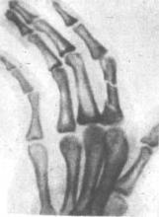

При переломах фаланг наблюдаются обычные признаки переломов костей: припухлость и кровоизлияние в области перелома, наличие деформаций, болезненность при пальпации области перелома и нарушение функции поврежденного пальца. Все эти признаки имеются при смещении отломков. Выраженная деформация отсутствует при переломах без смещения (рис.6, 7), трещинах и внутрисуставных повреждениях (9, с.89).

Рисунок 6 - Внутрисуставной перелом средней фаланги пальца.

Рисунок 7 - Перелом основной фаланги ІІ пальца (а) и двойной перелом (б).